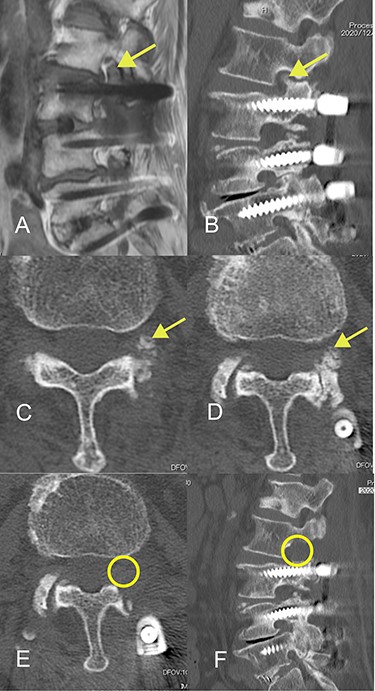

Histopathological examination of the resected specimen showed a degenerated ligamentum flavum and a distinctive ossified plaque within the ligamentum flavum. Chondrocytes were identified near the area of ossification but there was no cartilage cap to suggest osteochondroma. These findings indicated that the degenerated ligamentum flavum had been gradually replaced by ossified tissue via an endochondral ossification process (Fig. 4) and were considered sufficient to warrant a diagnosis of OLF.

(A) Hematoxylin and eosin-stained micrograph showing chondrocytes near the area of ossification (hash). Formation of bone in hyaline cartilage is indicated by osteoblasts (triangle). There was no cartilage cap, as would be found in osteochondroma. (B) Elastica van Gieson-stained micrograph showing sparse and degenerated elastic fibers in the ligamentum flavum.